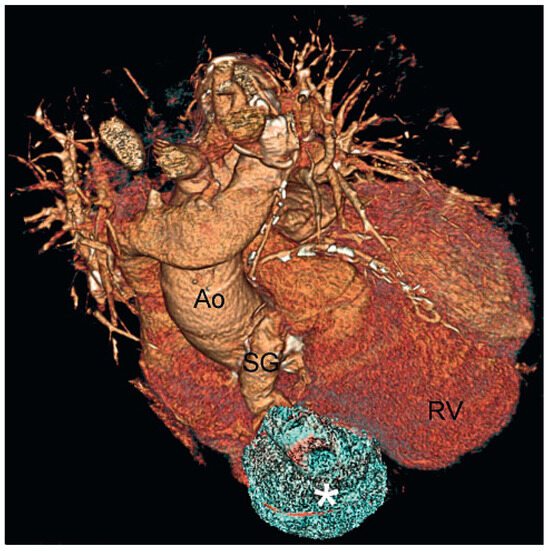

Understanding the pathways that chauffeur pathological remodelling in the failing heart still remains challenging. Myocardial inflammation is a common cause of pathological tissue remodelling in the heart promoting development of heart failures, ofte...